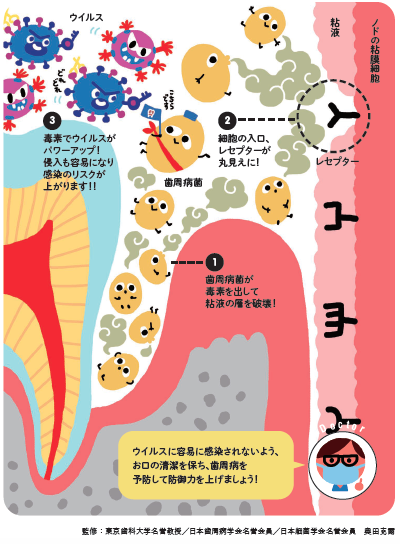

ウィルス感染は歯周病菌により口腔粘膜の細胞が破壊され、レセプターがむき出しになった細胞にウィルスが付着することで感染します。